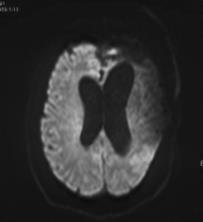

复阅2018年12月27日MRI片:左侧额颞部颅骨修补术后改变,两侧额颞叶、右侧小脑半球、左侧侧脑室后角旁均见长T1长T2异常信号,脑室系统扩大。提示左侧额颞部颅骨修补术后,两侧额颞叶、右侧小脑半球、左侧侧脑室后角旁软化灶形成。

图7-12,2018年12月27日MRI片,左侧额颞部颅骨修补术后,两侧额颞叶、右侧小脑半球、左侧侧脑室后角旁软化灶形成